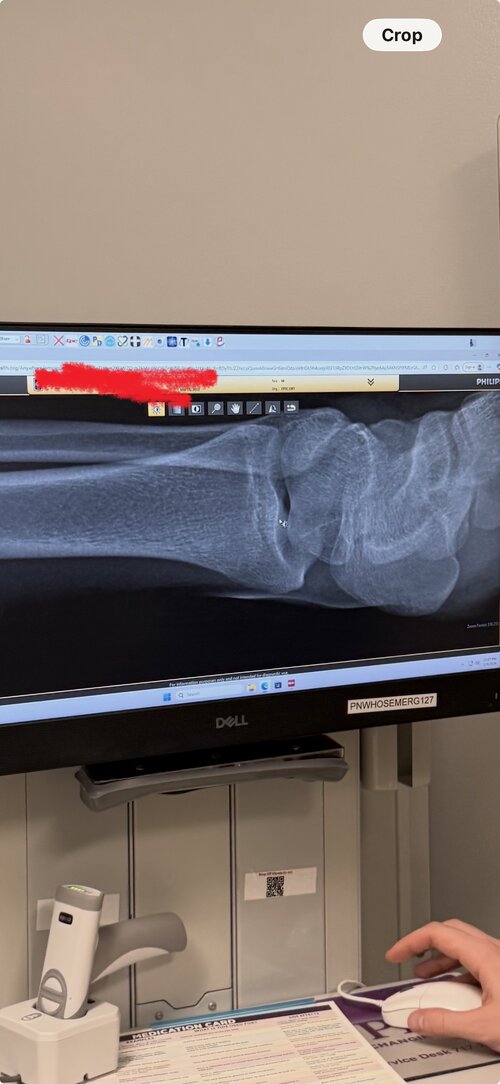

Are my growth plates closed? I’m planning on taking anastrozole

still opened, its so clear as well, what a retarded doctor

they're open, by the way.

How long u think i got?